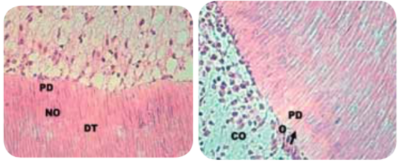

Preparo com CVDentus: Sem danos à membrana pulpo-dentinária. Preservação dos odontoblastos (CO), dentida tubular (DT), pré-dentina (PD) e zona acelular (ZA).